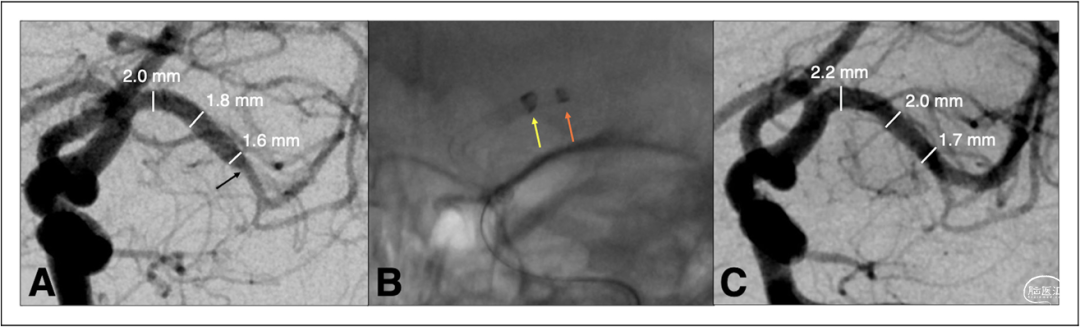

图1和图2显示了该研究中颇具挑战的血管解剖结构,包括多个>180°的成角和扭曲。该研究中使用的直径2.74mm的Zoom 88导管与直径较小的M1导管在尺寸上存在较大差异,但所有手术均未出现节段或明显的血管损伤(图3)。

图1.(A)一名NIHSS评分为26的成年患者出现M1远端闭塞(黑色箭头)。(B)使用Zoom 88(2.74毫米外径)(黄色箭头)和Zoom 71(橙色箭头)导航至M1,直接抽吸血栓。(C)血管造影显示Zoom 88机械取栓后M1再通达到TICI 3。